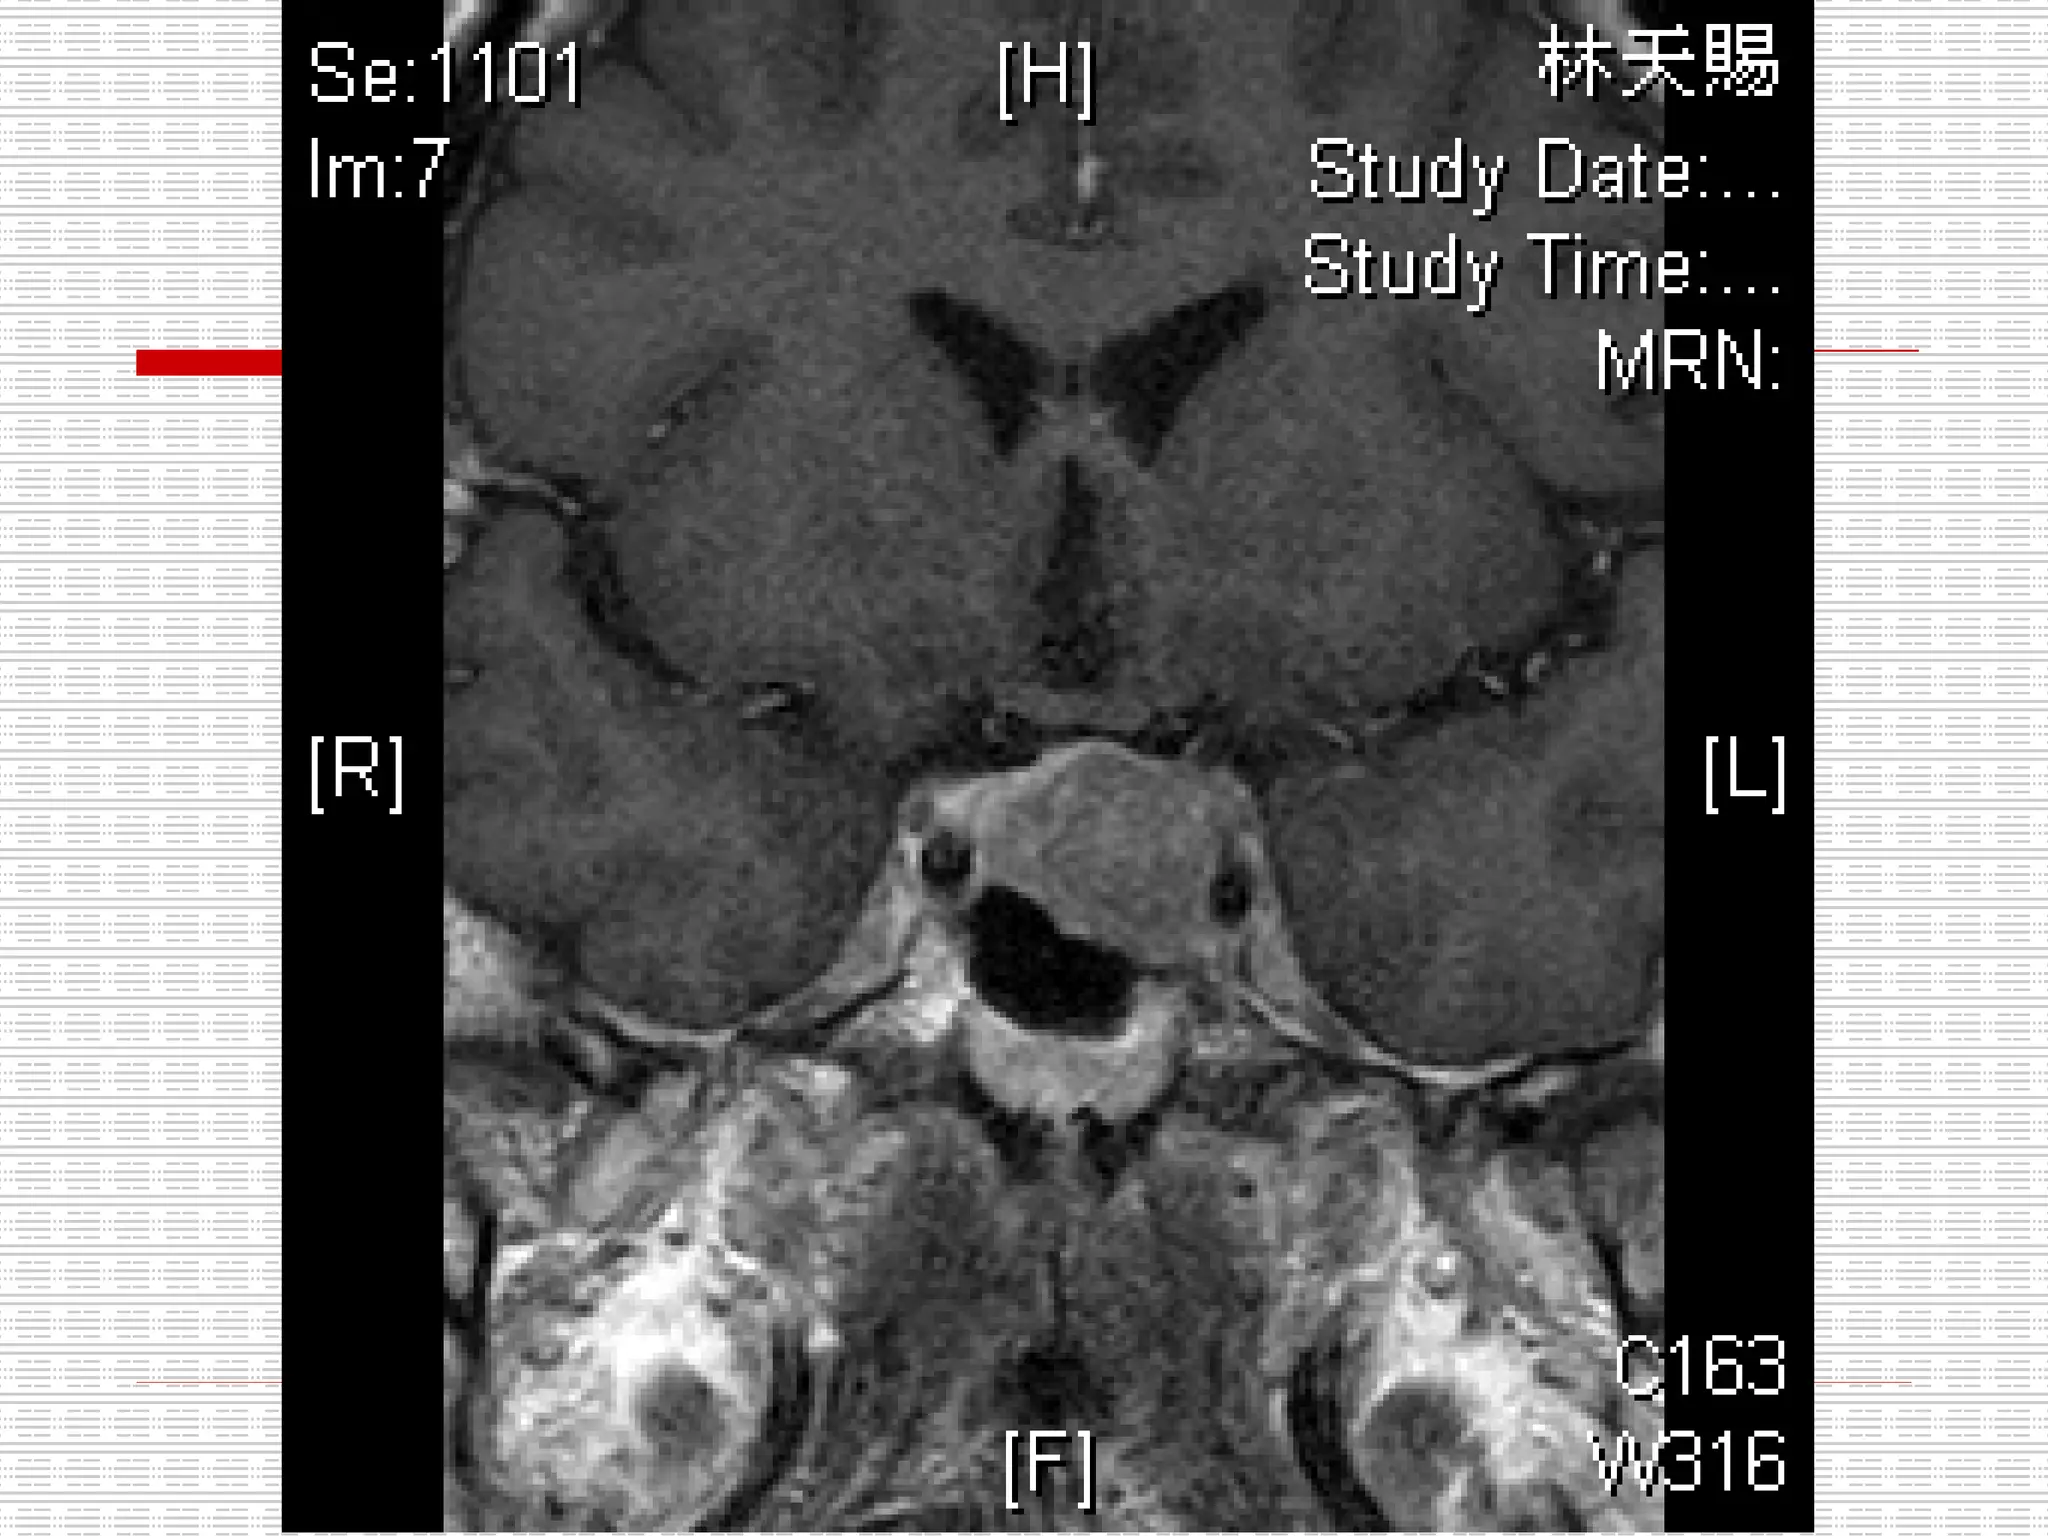

CT: Enlarged pituitary fossa with bony scalloping and soft tissue opacification

CT: Enlarged pituitaryfossa with bony scalloping and soft tissue opacification